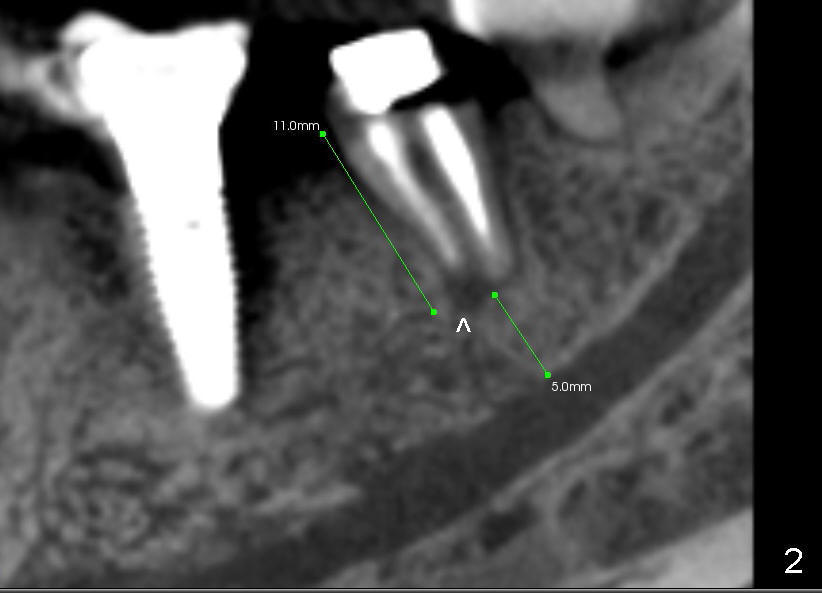

CBCT reveals periapical radiolucency (Fig.2 ^). The tooth appears to be nonsalvageable. The root is 11 mm long. There is 5 mm bone between the fused apex and the inferior alveolar nerve. The prospective implant is going to engage 3 mm out of the 5 mm native bone for primary stability.